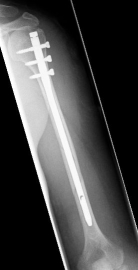

Picture: Here you can see a completely shifted upper arm fracture with a strong bend of the axis. First the operative treatment was performed by repositioning the bone and internal splinting of the fracture with a medullary nail.